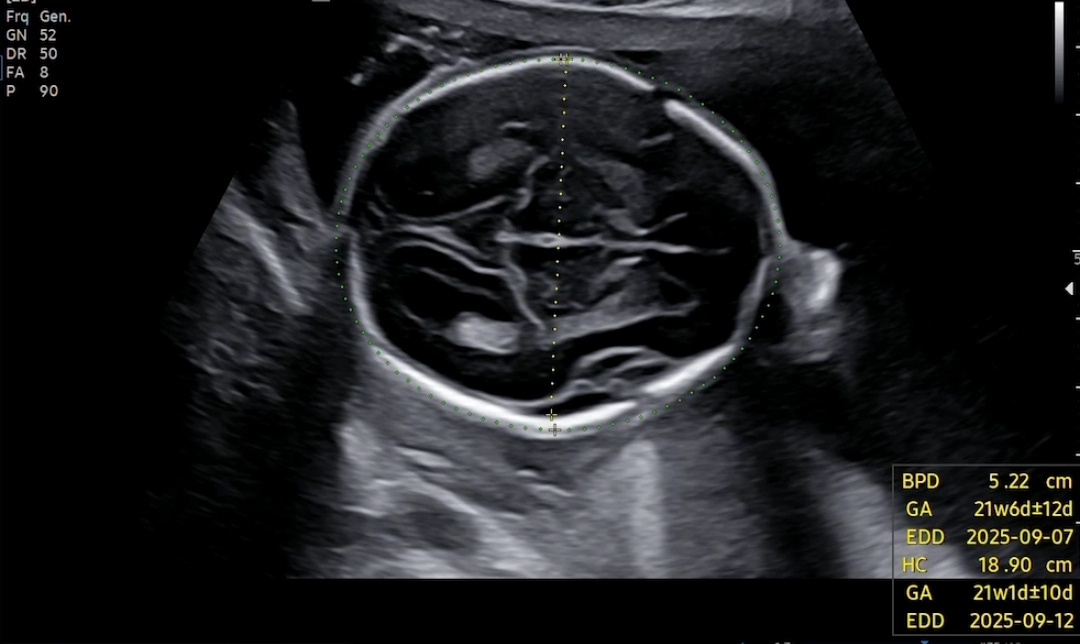

배초음파로 봤구요. 뇌부터 봤어요. 다행히 정상~ 뇌량이랑 이것저것 봐주시던데 전 봐도 뭐가 뭔지 전혀 모르겠더라구요..? ㅜㅜ